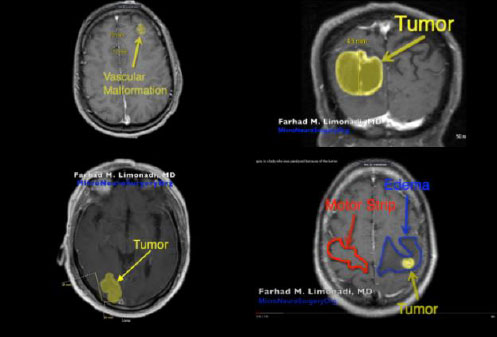

Subsequently, four YouTube craniotomy videos, Cavernoma [6], GBM [7], Metastatic Tumor [8], and Unknown Tumor [9] were extracted into MP4 files. Furthermore, the specific age and associated medical conditions for each patient’s video are displayed in Table 1. In addition, Fig. (6) illustrates the pre-operative MRI for each patient.

| Pathology | Age and Sex | Clinical Conditions |

|---|---|---|

| Cavernoma | ~40 year-old male | Three seizure episodes. Although these seizures were medically controlled, the patient requested surgical resection. |

| Glioblastoma Multiforme (GBM) | ~70 year-old male | Left homonymous hemianopsia and progressive confusion. This tumor was approximately 30 cubic centimeters in volume. |

| Metastatic Tumor | ~70 year-old female | Progressively growing mass in the right occipital lobe. The patient suffered from mild left homonymous hemianopsia. |

| Unknown Tumor | ~50 year-old female | Complete right-sided paralysis with a right-sided facial droop. |

As shown in the MRI images in Fig. (6), the craniotomy with the most visible edema, Unknown Tumor [9], had relatively small median CSS values which are presented in Figs. (14 and 15). This indicates that the presence of edema may cause significant reductions in CSS. Thus, edema may have resulted in the brain being less pulsatile, which subsequently may have reduced the observed CSS values.

Furthermore, GBM [7], which was a relatively large tumor, was strongly associated with a reduction in the magnitude of the observed CSS. This tumor may have resulted in an increase in intracranial pressure and, therefore, a reduction in pulsatility. Thus, we can infer that the reduced magnitude of the observed CSS may be indicative of a possible reduction in localized cerebral perfusion due to the compressive effect of the tumor.

In addition, the craniotomies of two small superficial tumors, Metastatic Tumor [8] and Cavernoma [6], had relatively large median CSS values.